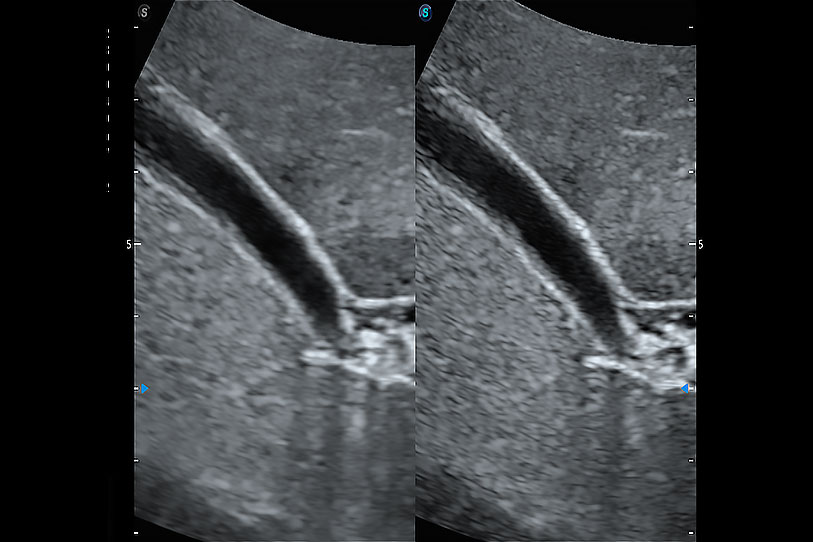

增強穿刺針在動物解剖結(jié)構(gòu)中的位置,提高穿刺介入的安全性和準確性。

操作簡便,無需高頻度外力作用即可真實反映組織的形變,快速評估腫瘤良惡性。